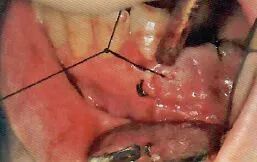

3 切开

利用手术刀·电刀等器械将手术区域的牙龈切开

医生利用手术刀进行切开。首先避免吸唾器在手术刀的切开路线上阻碍医生的操作。切开线设计分为三角形,四边形和沿牙龈缘等各种不同的形状。口腔卫生士一定要事先与医生确认切开设计的形状。

切开线设计(有残根的情况)

务必保证切开线区域的视的野晰度(切开前要吸引唾液,切开过程中要吸引血液)

切开前,一定要将切开线区域的唾液吸引干净。如果切开区域有唾液残留的话,会造成医生无法找到切开线路。切开时,从切开线区域会有血液溢出。将吸唾器放置到出血点,正确找到出血点才能更加有效的将溢出的血液吸引干净。